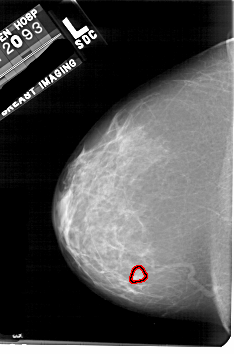

A_1758_1.LEFT_MLO

LEFT_MLO LINES 4861 PIXELS_PER_LINE 3346 BITS_PER_PIXEL 12 RESOLUTION 43.5 OVERLAY

FILE: A_1758_1.LEFT_MLO.OVERLAY

TOTAL_ABNORMALITIES 1

ABNORMALITY 1

LESION_TYPE MASS SHAPE LOBULATED MARGINS OBSCURED

ASSESSMENT 3

SUBTLETY 4

PATHOLOGY BENIGN

TOTAL_OUTLINES 1

BOUNDARY